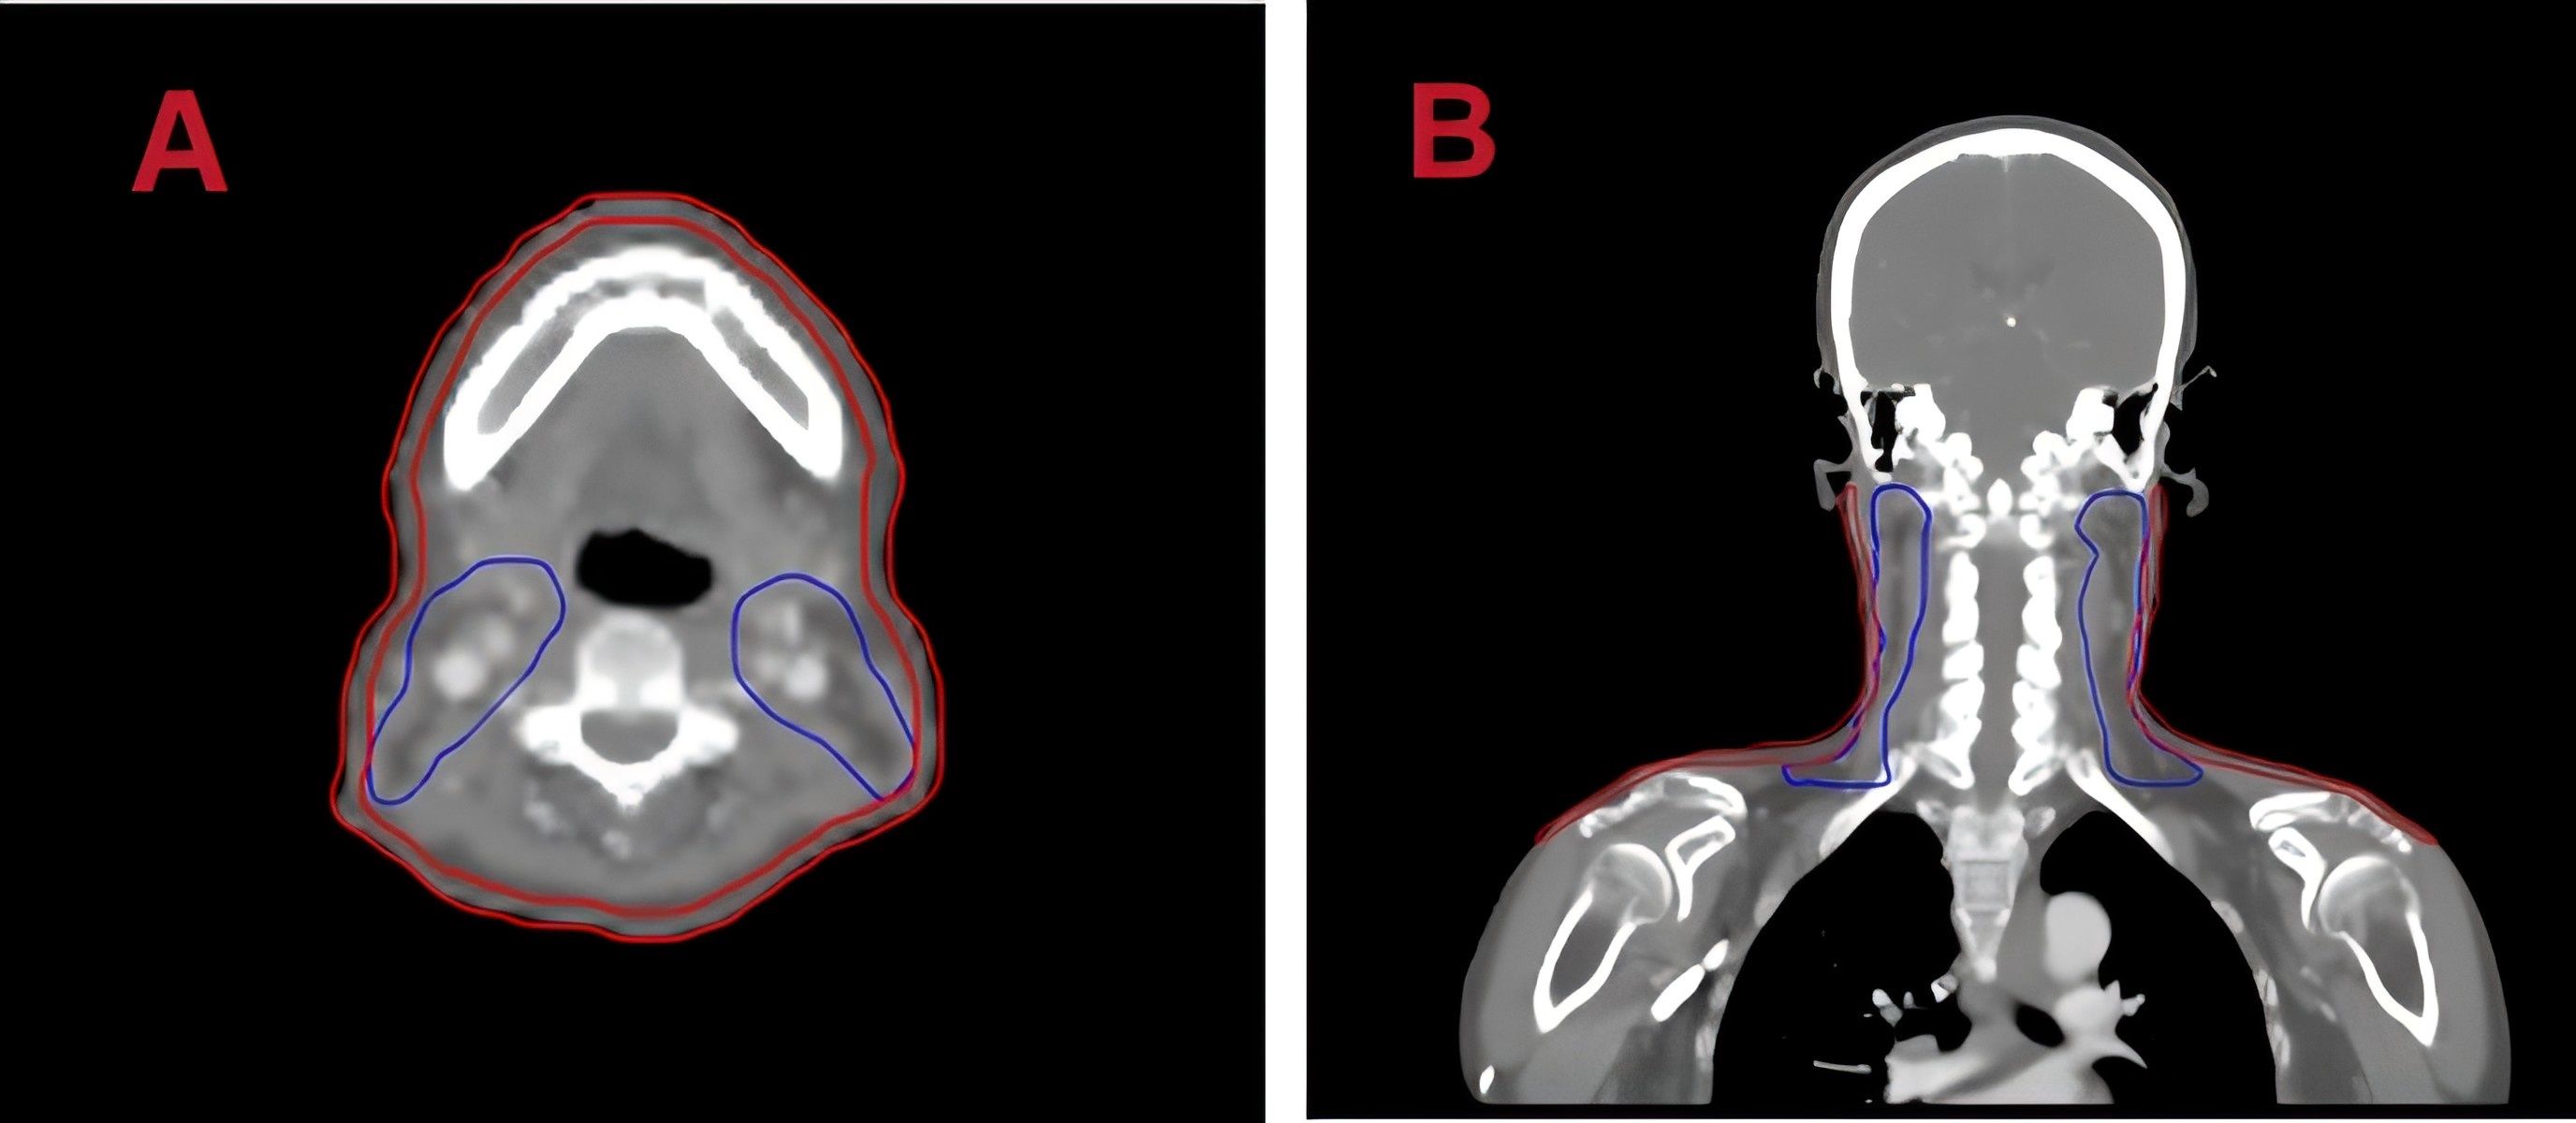

Positional CT scans were performed using a Philips Brilliance large-bore CT scanner. Patients were immobilized in the supine position using thermoplastic masks and customized foam. The tube voltage was set to 120 kV, X-ray tube current was 225 mA, CT slice thickness was 3mm, and scan resolution was 512 × 512 pixels. To analyze the dose distribution in the patient’s superficial skin layer, ring - shaped structures were automatically generated as regions of interest(ROIs) by subtracting 3 millimeters from the patient’s surface. The upper and lower boundaries of these ROIs were consistent with the upper and lower boundaries of the planning target volume for the lymph nodes (PTV-ND), as shown in the delineated ROI figure (Figure 1).

Figure 1. Regions of interest (ROI) on planning CT images. (A) Axial and (B) coronal views with skin delineated in red.